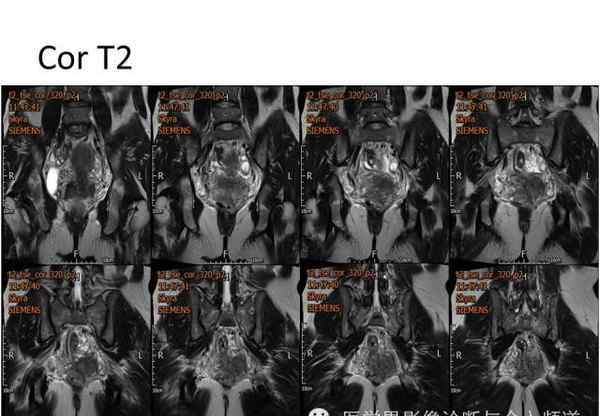

核磁共振平片扫描和增强扫描显示:

盆腔内可见弥漫性长T1长T2异常信号,FS-T2WI可见高信号,涉及直肠左前壁、直肠侧韧带和宫颈等。边界不清,盆腔可见条带状FS-T2WI高信号强度。注射钆喷酸葡胺后,病情明显加重。